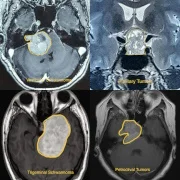

At our advanced Neurosurgery Center in Thane, we specialize in brain tumor surgery with a focus on both complete tumor removal and the preservation of neurological functions. Using modern techniques such as microsurgery, endoscopic brain surgery, and neuronavigation systems, our neurosurgeons ensure safe and precise treatment. Whether it is a glioma, meningioma, pituitary tumor, or metastatic brain tumor, we provide personalized surgical care for the best outcomes. Patients benefit from shorter hospital stays, faster recovery, and improved quality of life after surgery.

– Pediatric Brain Tumors

– Skullbase Tumors